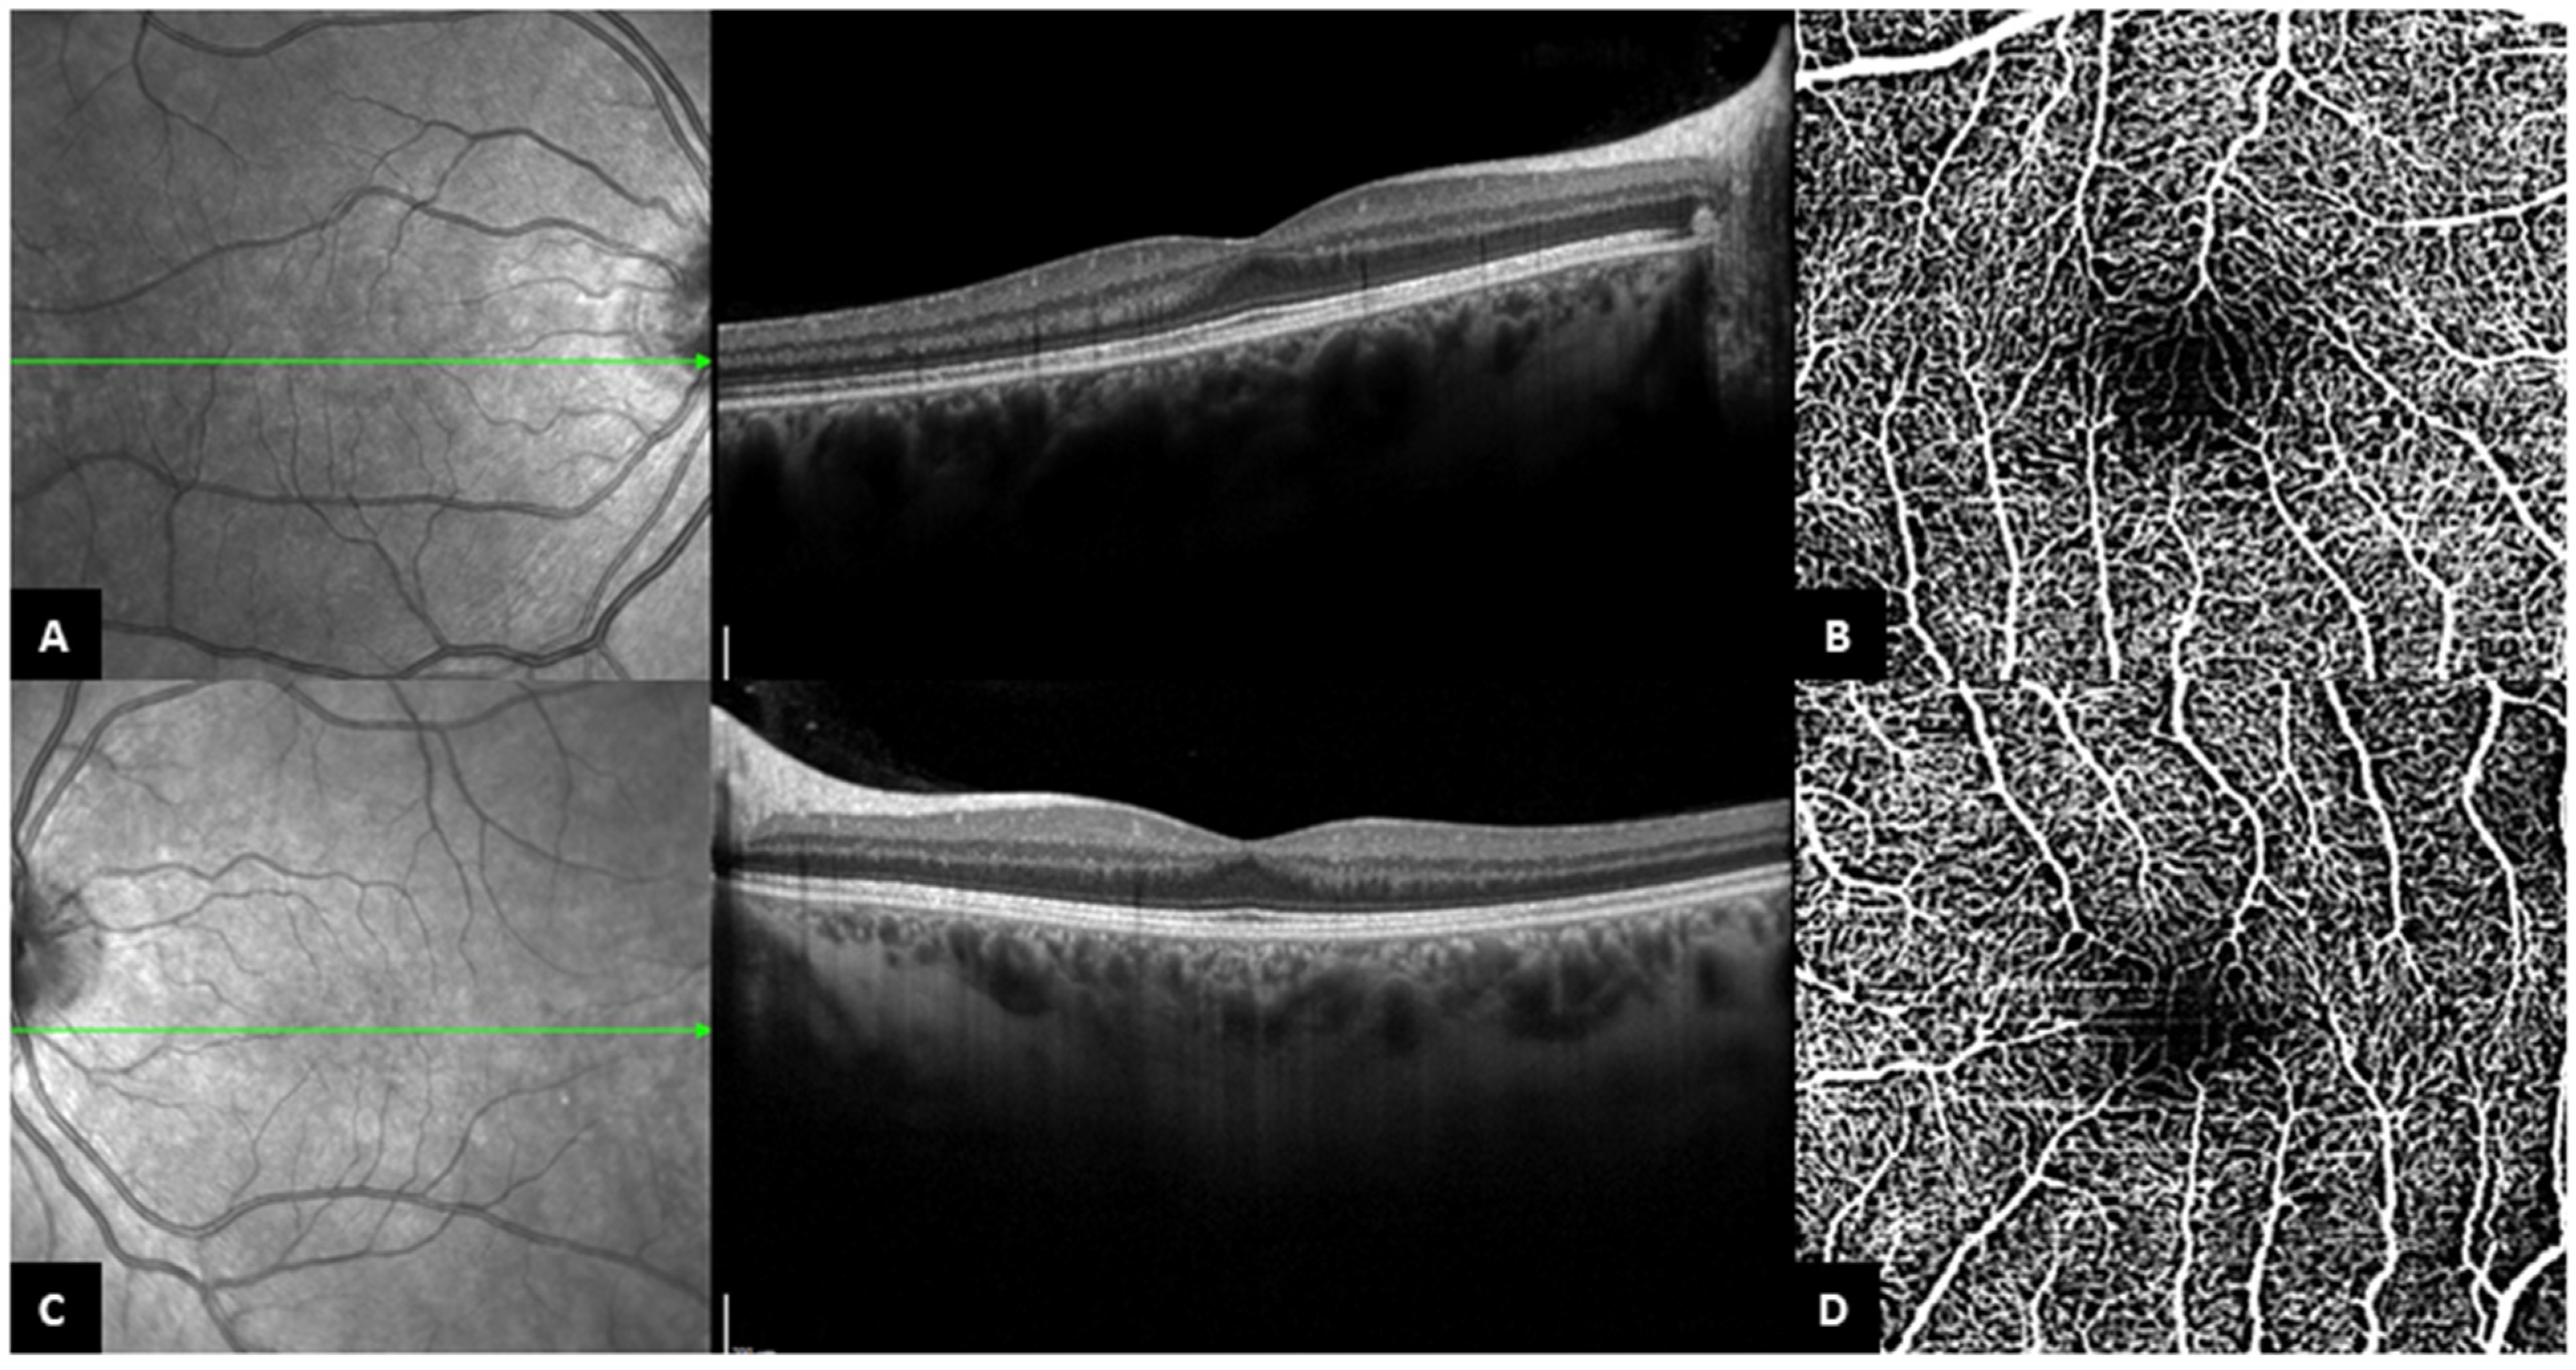

Figure 3. Patient 18. (A,C). Central OCT B-scan of the right eye and the left eye, with persistence of the inner retinal layers. (B,D). OCT-A from the same patient, ((B). right eye, (D). left eye), with bridging vessels across the foveal avascular zone (the slabs contain the superficial and deep capillary plexuses together).

All but two of the eyes with FP in our cohort had atypical foveal hypoplasia. Patient 18 is the only patient that had grade 1b foveal hypoplasia in both eyes, while she presented none of the clinical features of Best disease (Figure 3). Diagnosis of BVMD was established based on familial history and genetic testing in this young woman. This particular case supports the hypothesis that the mechanism of the fovea plana is neither dependent on the deposition of the material nor the stage of the disease. Considering this, we believe that the presence of foveal hypoplasia should increase the suspicion of Best disease in children with a positive familial history of BVMD, even before the appearance of vitelliform material deposition. Furthermore, our observations in patient 18 suggest that the ‘atypical’ aspect of foveal hypoplasia might appear as the disease progresses, with secondarily acquired disruption of external retinal layers.

3.3. OCT-A Findings